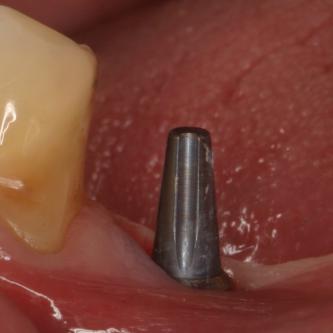

Exemple 3: Un implant à la place d'une incisive latérale supérieure droite. Sur cette image on voit le moignon en titane qui est vissé sur l'implant.